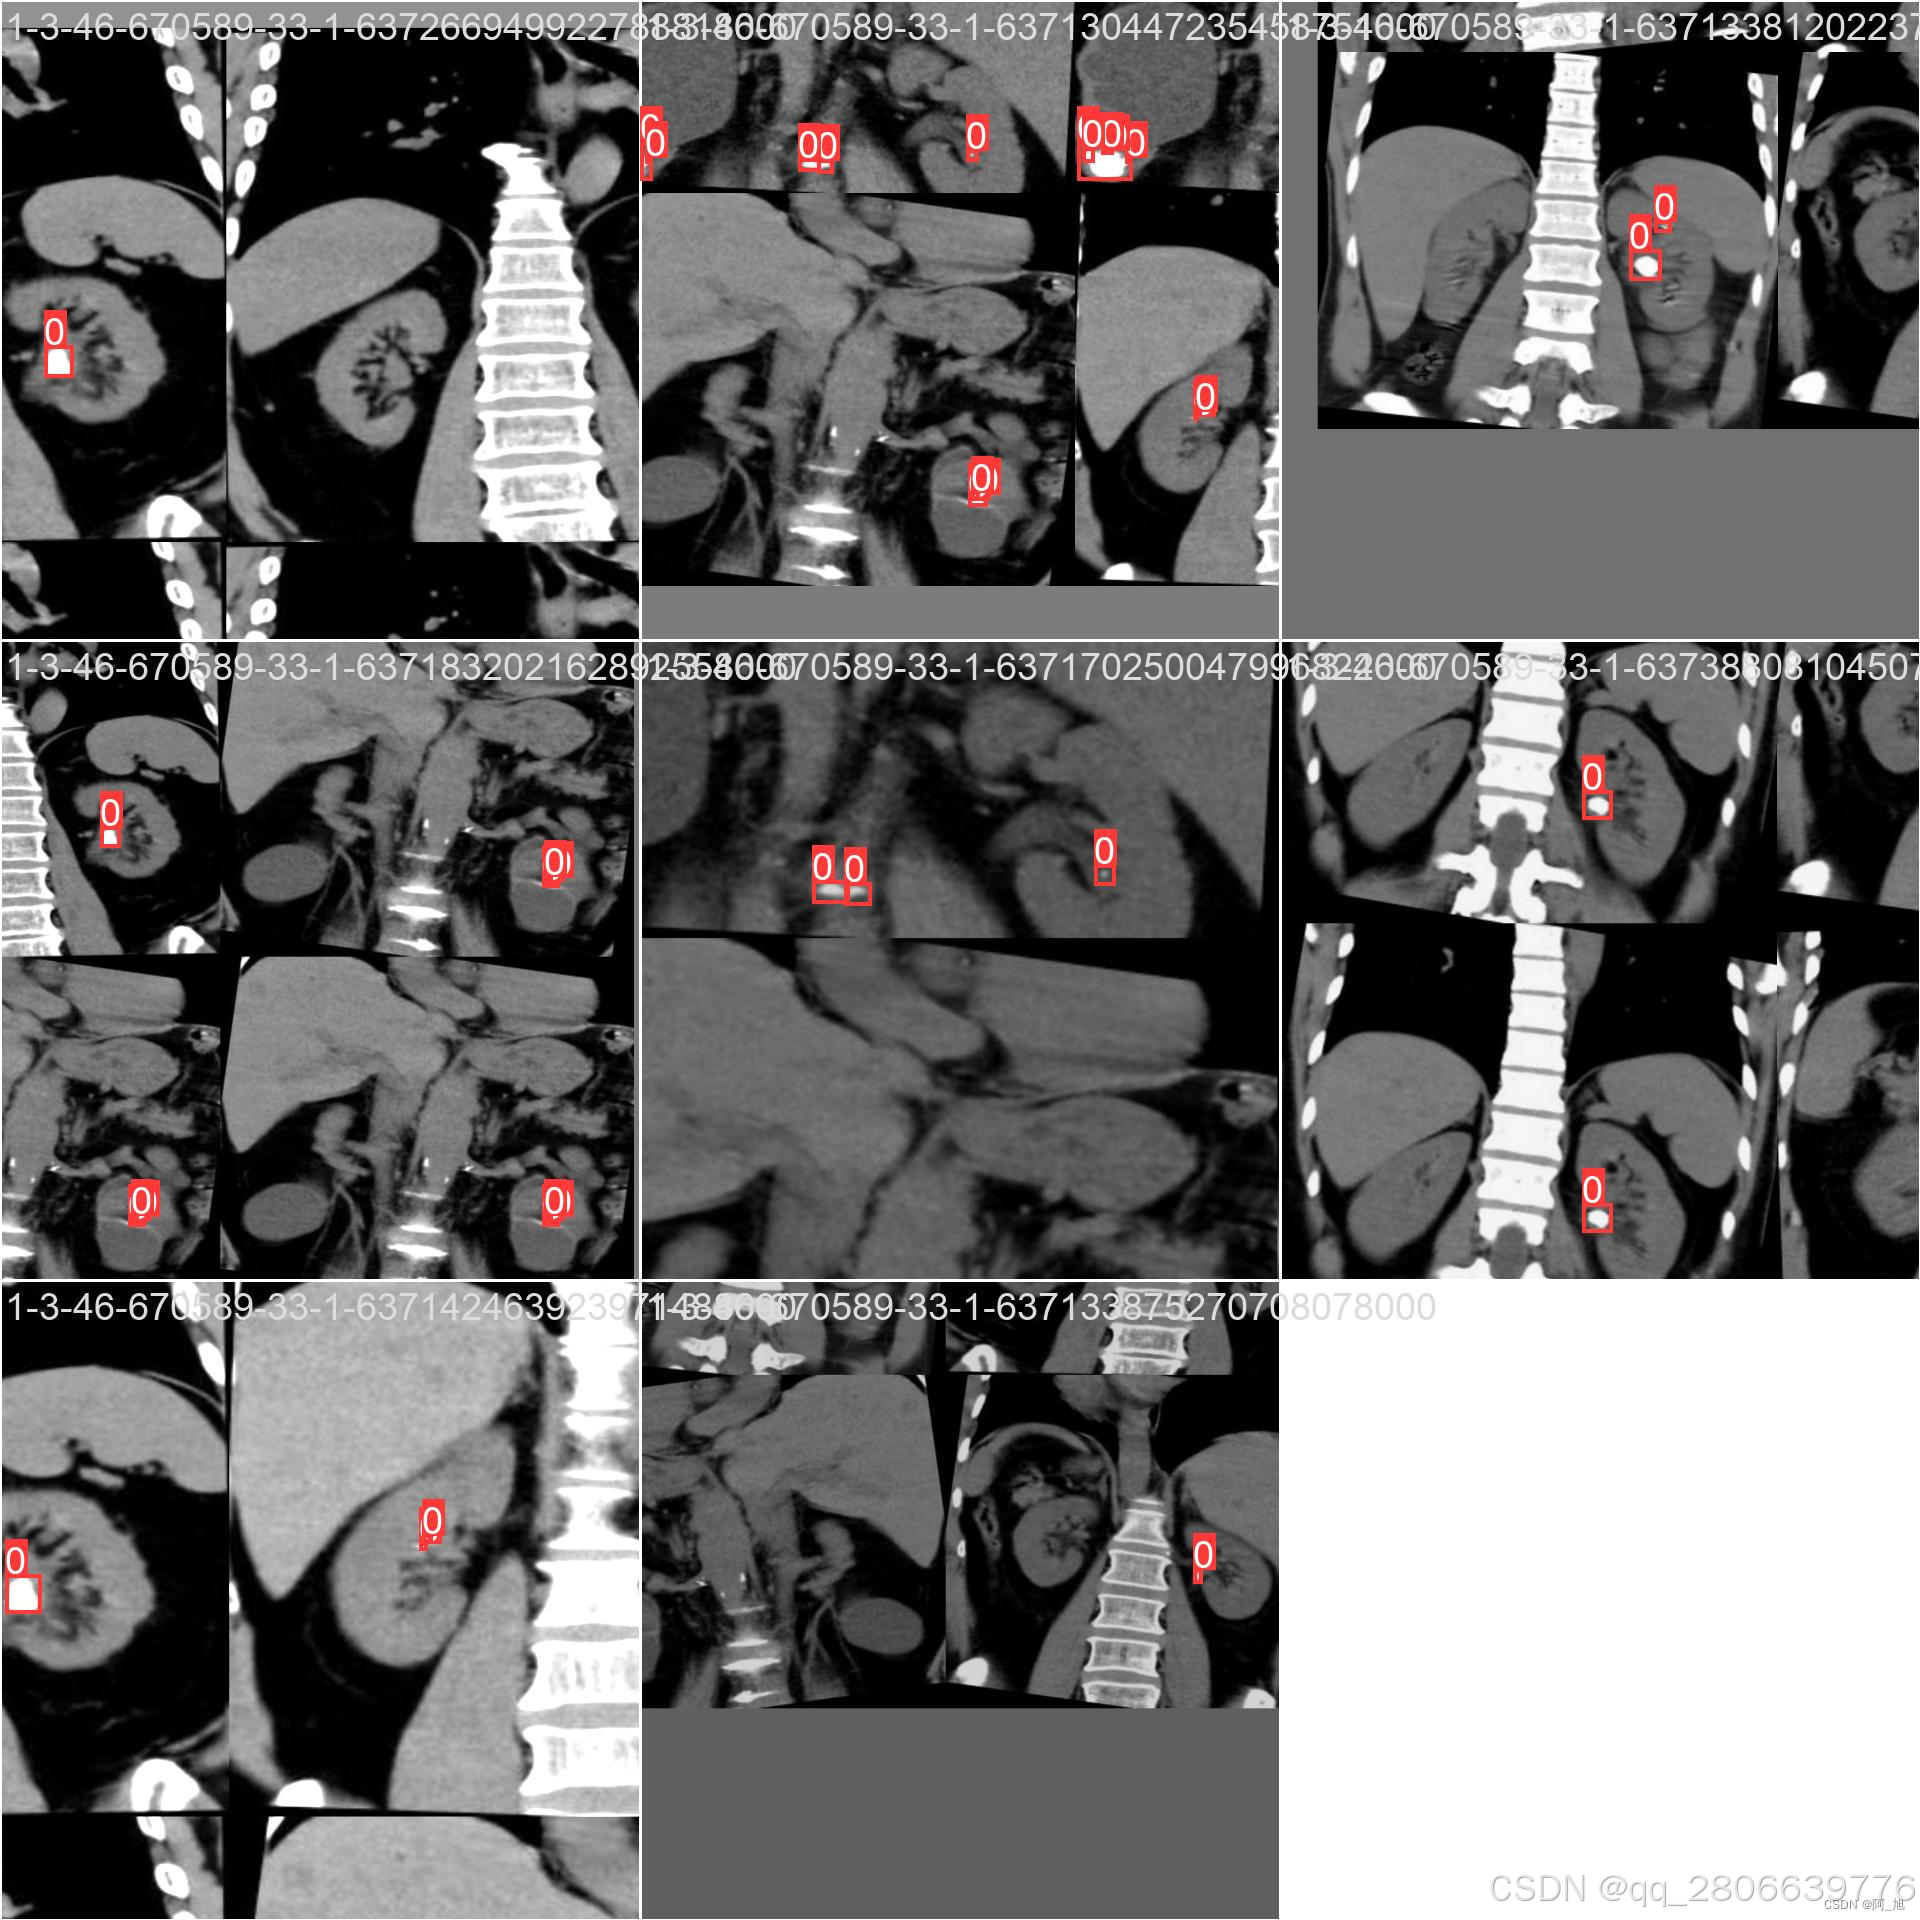

CT扫描图像的肾结石智能检测系统在医疗诊断方面提供了一种快速、准确的辅助工具,显著提高了医生识别和评估肾结石的效率。本文基于YOLOv10深度学习框架,通过1300张CT扫描的肾结石相关图片,训练了一个进行肾结石目标检测的模型,可以对CT扫描图像中的肾结石进行实时检测。并基于此模型开发了一款带UI界面的肾结石智能检测系统,更便于进行功能的展示。该系统是基于python与PyQT5开发的,支持图片、视频以及摄像头进行目标检测,并保存检测结果。本文提供了完整的Python代码和使用教程,给感兴趣的小伙伴参考学习,完整的代码资源文件获取方式见文末。

部分截图如下: